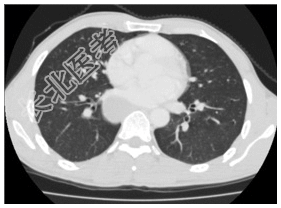

- [材料题] 患者,男性,31岁。阵发性胸痛多年,近来明显。查体:双肺呼吸音清,未闻及干湿性啰音。腹平软,肝脾未扪及。行胸部CT平扫及增强检查。

- 简答题1、患者的诊断及依据是什么?

- 简答题2、鉴别诊断有哪些?